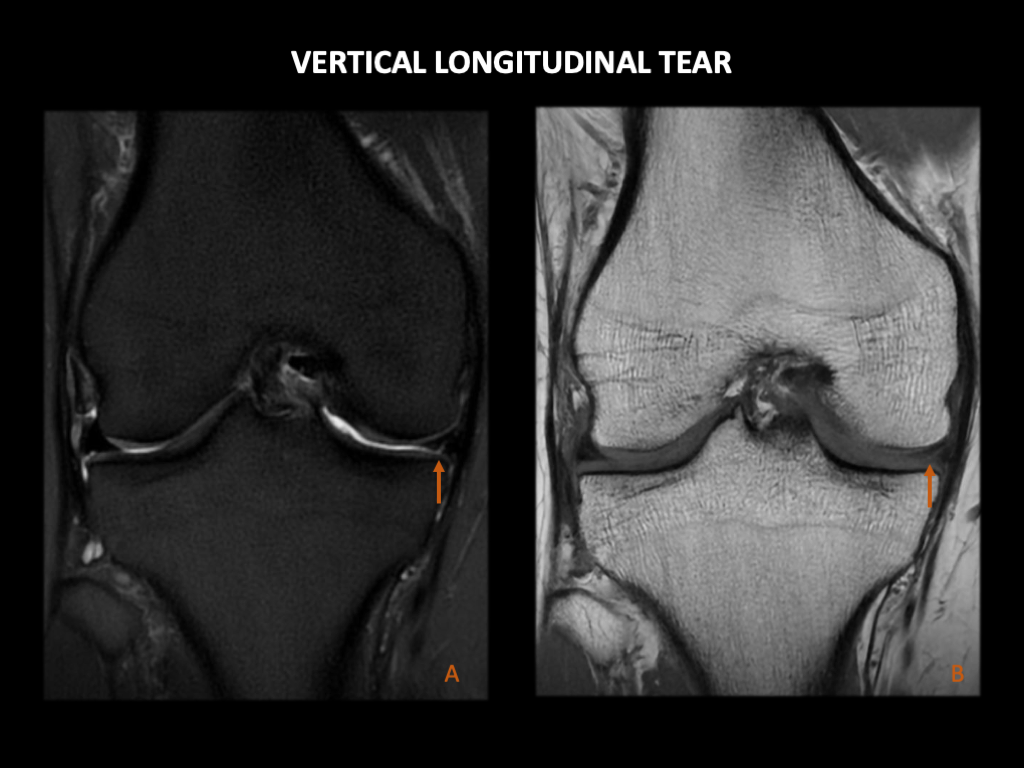

垂直撕裂:这些通常发生在半月板的体部。当它们影响到内侧半月板的后角时,可能适用Ramp损伤的分类。

图 6:一名30岁男性,有膝关节疼痛。右膝3T MRI:(A) 冠状位抑脂T2WI序列和 (B) 冠状位T1WI显示内侧半月板主体部见高T2线性信号,延伸至半月板胫骨表面(箭头所示)。